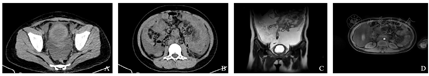

辅助检查:入院查血常规:白细胞计数16.65×109/L,嗜酸性粒细胞百分比30.4%,嗜酸性粒细胞计数4.99×109/L,血小板计数705×109/L。尿常规:酮体阳性(++++),潜血弱阳性(±),白细胞定量48个/μL,结晶475个/μL。凝血功能:FDP 33.23 μg/mL, D-D 12.5 μg/mL。肿瘤标记物:CA125 139 U/mL,人附睾蛋白469.0 pmol/L,铁蛋白237 ng/mL。25-羟维生素D 6.0 ng/mL。血细胞质量分析:中性分叶核粒细胞51%,嗜酸性分叶核粒细胞20%,成熟淋巴细胞28%,成熟单核细胞1%。腹水常规:颜色黄色,透明度微浑,凝固性无凝块,红细胞计数3 000×106/L,白细胞计数7 706×106/L,单个核细胞百分比9%,多个核细胞百分比91%,黏蛋白定性试验阳性(+);细胞学检查:有核细胞量多,以中性粒细胞为主,可见嗜酸性粒细胞(20%)、嗜碱性粒细胞(4%)。腹水生化:总蛋白43.4 g/L,碱性磷酸酶47.0 U/L,血糖4.79 mmol/L,乳酸脱氢酶218 U/L,腺苷脱氨酶6.3 U/L。腹水细菌涂片:未查到细菌。腹水细菌培养:无细菌生长。痰、尿、血培养:未见病原菌生长。骨髓涂片结果:未见任何异常细胞或寄生虫;粒系增生活跃,成熟嗜酸性粒细胞偏高占30%。骨髓活检结果:免疫组织化学:嗜酸性粒细胞增多,未见幼稚细胞及淋巴细胞增多,巨核细胞少见;流式细胞免疫荧光分析:CD34+细胞占有核细胞比例约0.50%,其免疫表型未见明显异常,粒细胞相对比例增多,其免疫表型CD13、CD15、CD16、CD11b未见明显表达紊乱,可见约40.6%的嗜酸性粒细胞;淋巴细胞相对比例减少,其中T细胞占淋巴细胞的72.0%,CD4∶CD8=1.77;NK细胞占淋巴细胞5.96%;成熟B淋巴细胞占淋巴细胞19.88%。骨髓染色体核型分析:46,XX,未见克隆样结构和数目异常。融合基因BCR/ABL、PDGFRB、PDGFRA、FGFR1、JAK2均阴性。寄生虫血清学检查:血吸虫、肺吸虫、囊虫、旋毛虫、肝吸虫、裂头蚴、包虫均未检出。过敏原检测均阴性。总IgE正常。粪便常规、生化全项、红细胞沉降率、降钙素原、T细胞亚群检测、免疫球蛋白、风湿二项、甲功五项、术前八项均正常。自身抗体全项、72 h结核菌素试验、结核γ干扰素实验、呼吸道病毒抗体8项均阴性。动态心电图监测未见明显异常。心脏彩超提示三尖瓣反流(少量)、心包积液(少量)。腹部彩超提示腹水大量,最大深度位于下腹部约73 mm。胸部CT提示:右肺散在结节;左肺上叶局限性肺不张;双肺多发索条;心包积液;双侧胸腔少量积液(图1)。全腹CT及泌尿系MRI+MRU提示:膀胱壁弥漫性不均匀增厚;腹膜弥漫增厚;腹盆腔大量积液;肠系膜根部、腹膜后、双侧腹股沟及髂血管旁多发肿大淋巴结(图2)。

A:腹部CT横断位示膀胱壁弥漫性不均匀增厚、双侧腹股沟及髂血管旁多发肿大淋巴结;B:腹部CT横断位示腹膜弥漫增厚,肠系膜根部、腹膜后多发肿大淋巴结;C:泌尿系核磁共振T2冠状位示膀胱壁弥漫性不均匀增厚、腹盆腔大量积液;D:泌尿系核磁共振T2横断位示腹腔多发肿大淋巴结。